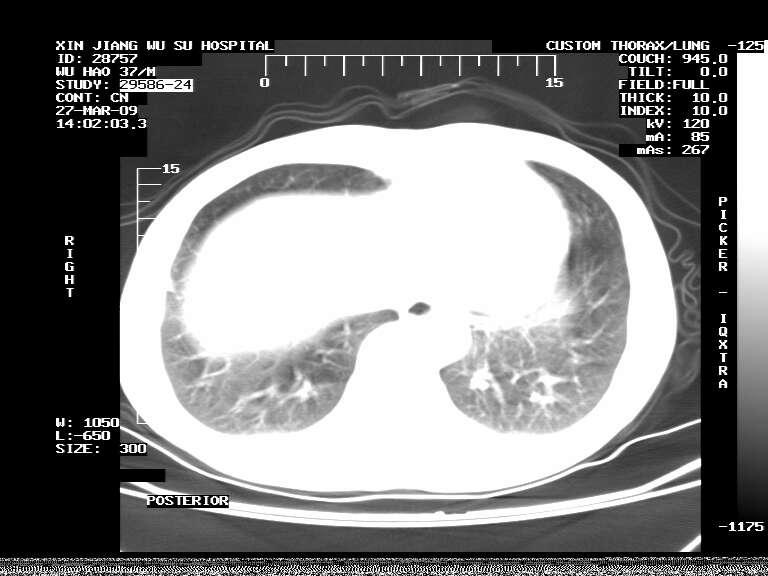

男,37岁,体检胸透发现阴影。

患者体检发现 无症状 左肺下叶占位,边缘模糊,可见血管聚束、分叶、胸膜牵拉,增强呈不均匀性强化。 首先考虑左肺下叶周围型肺癌,建议穿刺活检。

患者体检发现 无症状 左肺下叶占位,边缘模糊,可见血管聚束、分叶、胸膜牵拉,增强呈不均匀性强化。 首先考虑左肺下叶周围型肺癌,建议穿刺活检。支持!

左肺下叶见一结节病变,边缘欠清不光滑,与胸膜粘连且胸膜局限性增厚,注药后呈环形强化,动脉期壁呈明显点环状强化,静脉期壁强化减低,中心密度低无强化,灶周无明显的卫星灶和水肿区(晕征)---考虑周围性肺癌,不除外感染性病变,建议穿刺活检。

左肺下叶结节影.密度不均,边缘不规则.周围少许渗出.考虑感染性病变.结核?肿瘤待排.

左肺下叶软组织病灶,密度较高,内见点状钙化,其周围见子灶,邻近胸膜扁平样增厚.c+病灶强化明显,中心强化弱.诊断:左肺下叶结核瘤.

左肺下叶大片实变影,内靠胸膜见不规则更高密度结节灶,边缘强化,相邻胸膜增厚,胸膜下脂肪线存在。考虑炎症,结核可能。